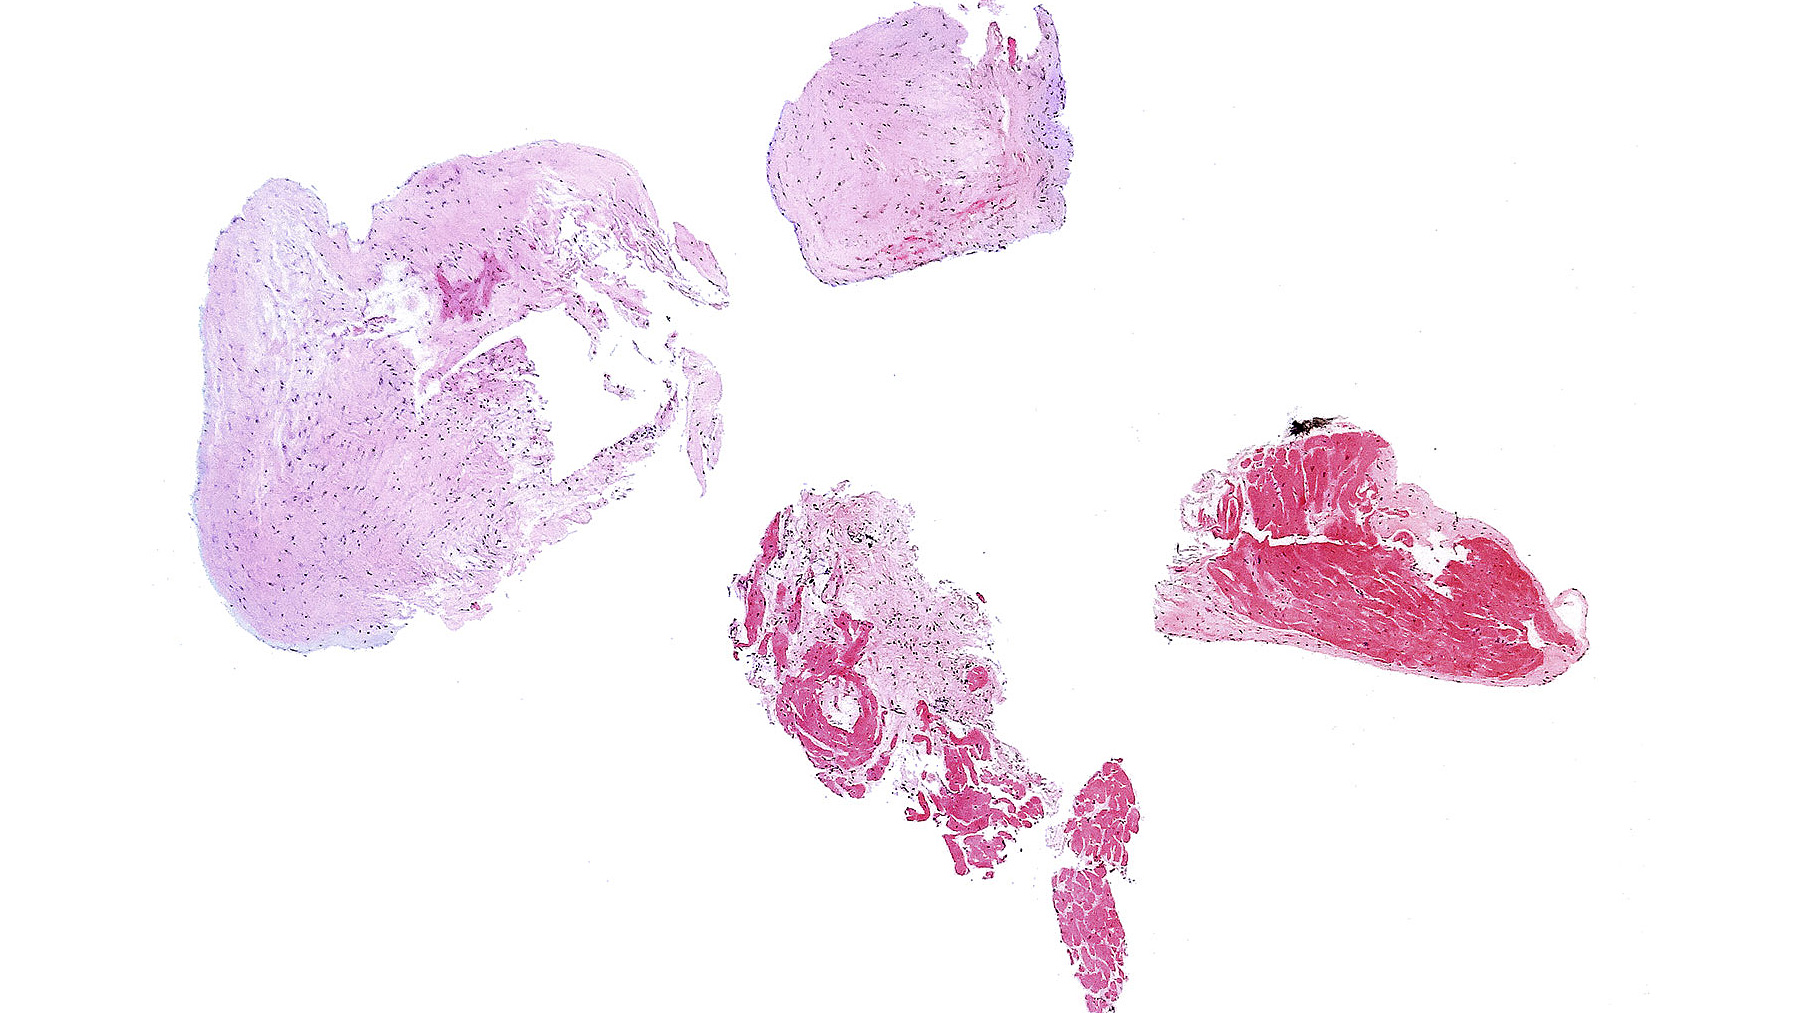

Figure A.

Suboptimal biopsy with >50% scar tissue

consistent with previous biopsy site (2x)

Figure B. Allograft myocardium with no evidence of cellular or antibody allograft rejection

Clinical History: 59 year-old female, status post orthotopic heart transplant one year ago secondary to adriamycin induced cardiomyopathy. Her previous biopsies were with no signs of rejection.

Histology: Images for suboptimal biopsy (Figure A) and normal myocardial tissue from a different heart allograft (Figure B) are presented as references.  Patient's sections with H&E staining (Figures C & E) show perivascular mononuclear cell infiltration with a single focus of associated myocyte damage consistent with mild acute cellular rejection, ISHLT 2004 Grade 1R (ISHLT 1990 Grade 1A). Trichrome staining from consecutive sections from C & E (Figures D & F) reveal mild interstitial edema.